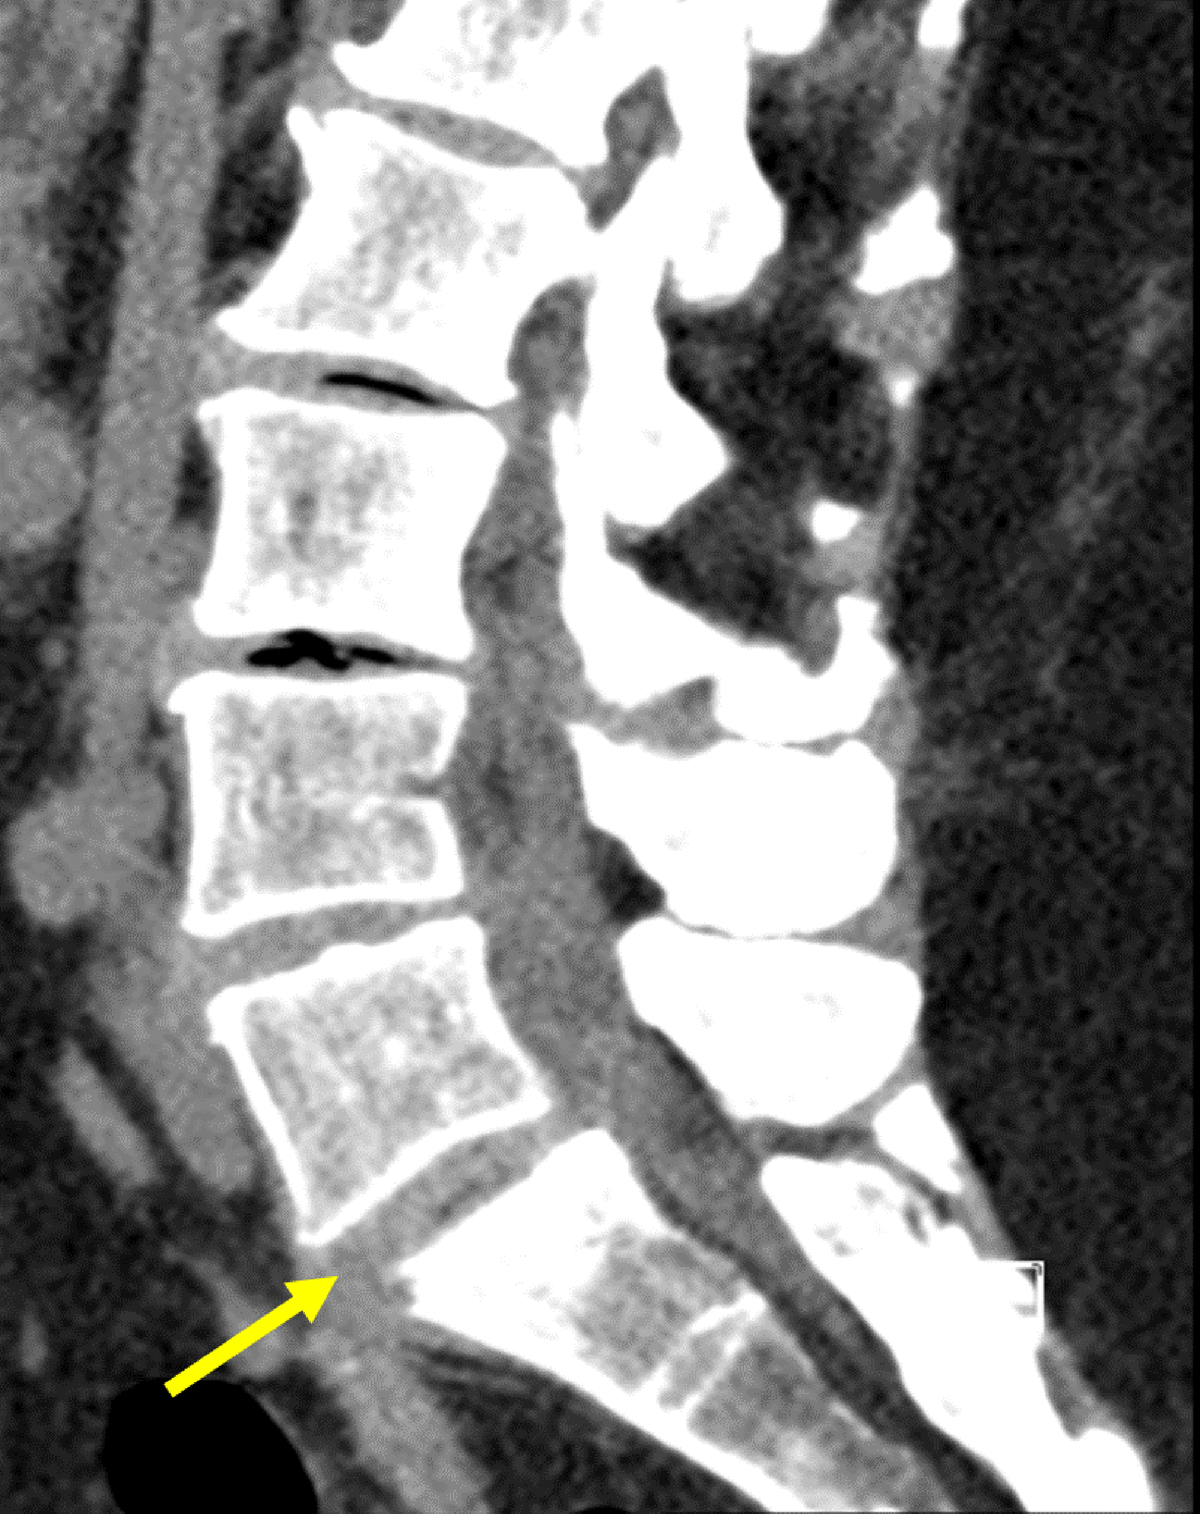

Figure 1

Sagittal non-contrast CT of lumbar spine: Initial CT-scan showing collection from L5-S1 disk with fistulation downwards, an anterolisthesis of L5-S1 with inter-apophysary posterior arthritis and a compression of the right root of S1 by the intervertebral disk.